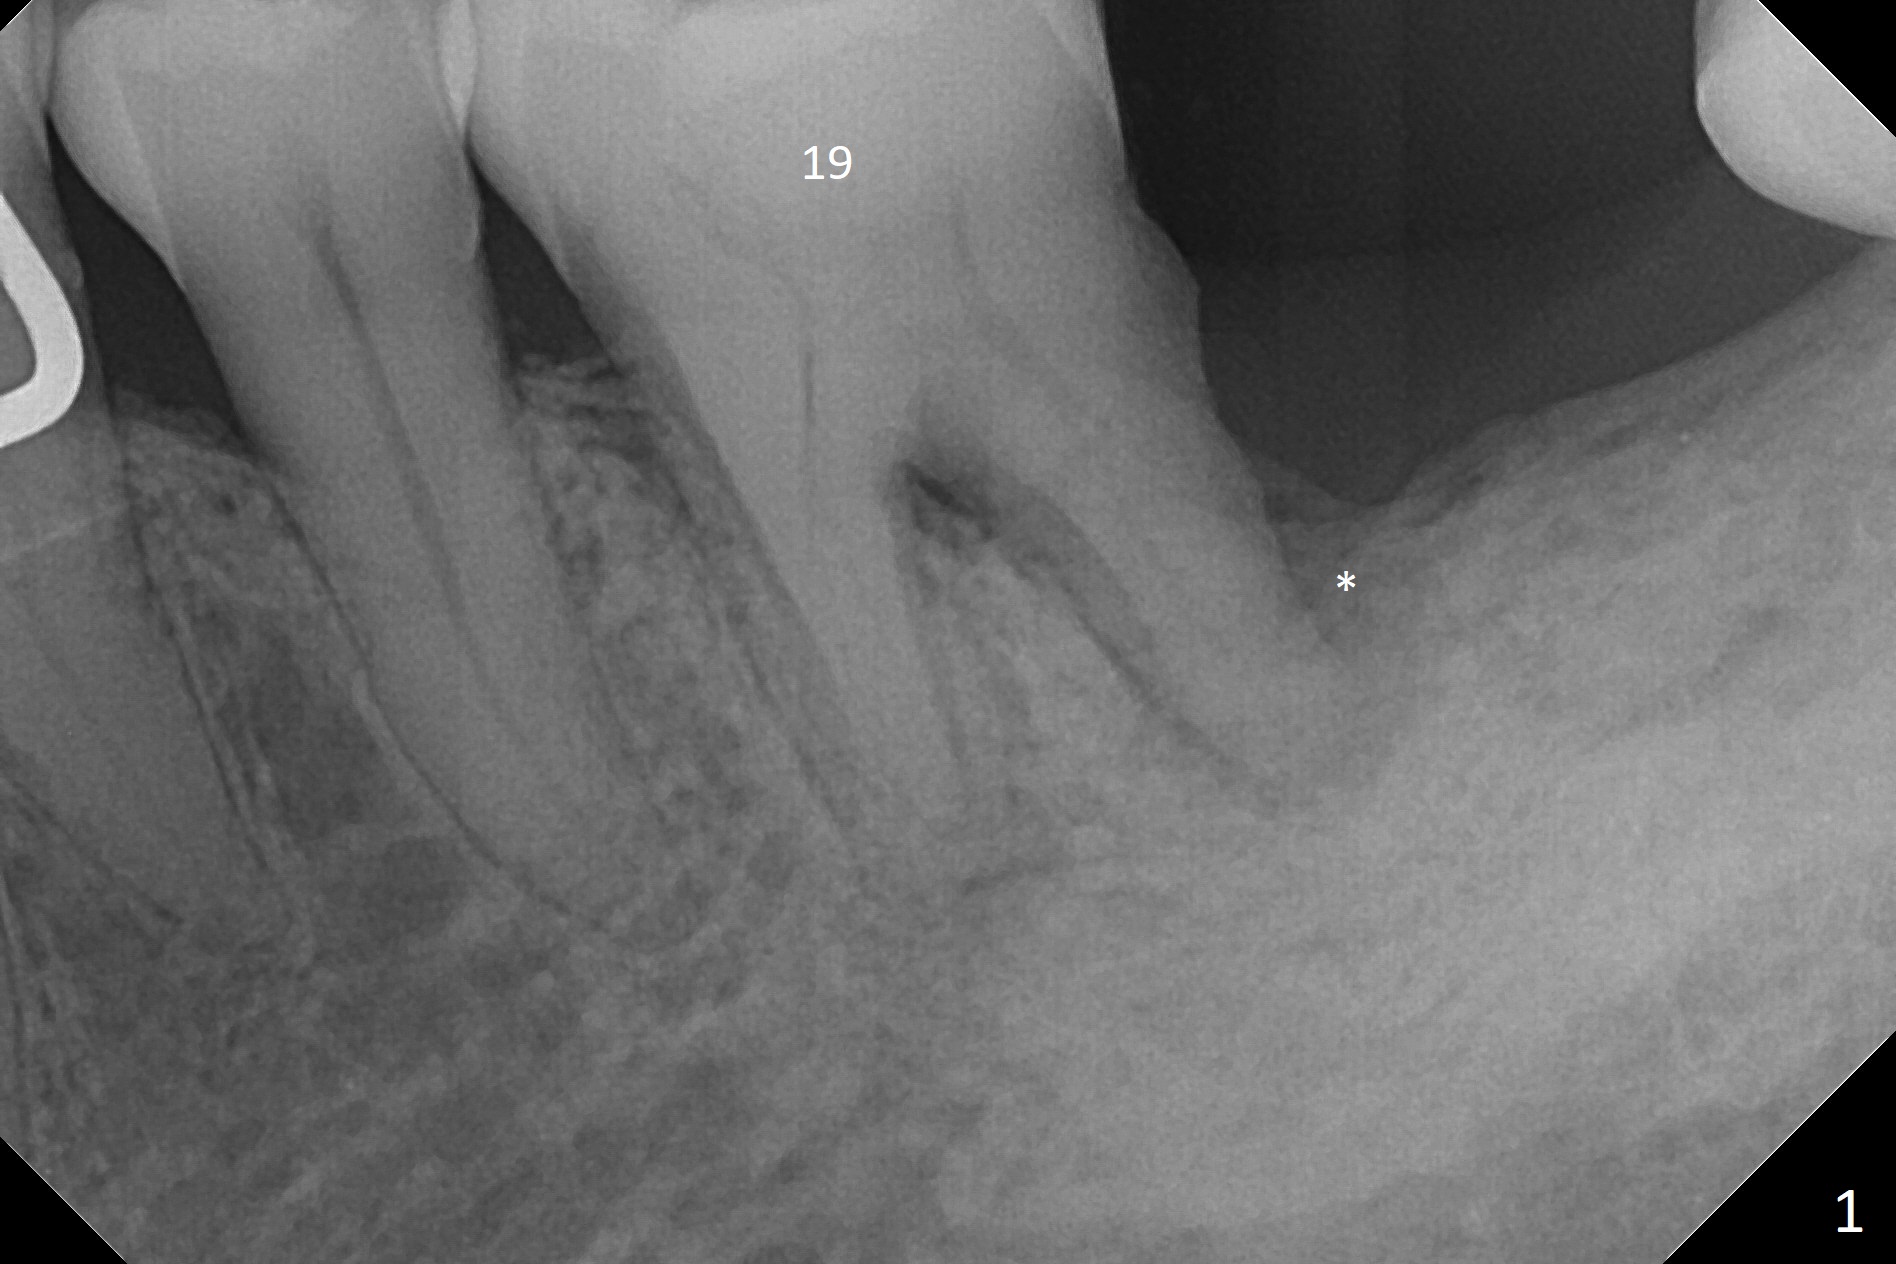

A 68-year-old man returns for extraction of the tooth #19 with distal root periodontal-endodontic lesion (Fig.1 *). After discussion, he agrees immediate implant. A 4.5x11.5 mm implant will be placed in the mesial socket (Fig.2 (red line: superior border of Inferior Alveolar Canal)); the plateau level with the septal crest (<). Osteotomy is initiated in the lingual slope of the mesial socket; the depth is controlled with stopper (Fig.3 S). The implant is placed at the level as expected (Fig.4 <) with insertion torque ~30 Ncm; after placement of 5.7x4(3) mm abutment and Osteogen plug (P) in the apical half of the distal socket, bone graft (G) is placed in the remaining socket gaps, mainly distal and buccal. An immediate provisional is fabricated to keep the graft in place (Fig.5 T). The graft may be lost if the gingival margin recedes in healing. Periodontal dressing is applied for additional security (Fig.6). There is no postop paresthesia. The upper border of the Inferior Alveolar Canal in Fig.3,4 seems to be high. In fact it may be a branch of the Inferior Alveolar Canal (Fig.7 yellow line, as compared to Fig.4). With all of measures taken (including periodontal dressing), the distal bone graft (Fig.8 *) is ~ 2 mm coronal to the crestal bone (red line) 6 months postop. The temporary crown is perforated. The gingival cuff is erythematous. A 6.8x5 mm healing abutment is installed. When the patient returns for impression, a 4.5x5.5(3) mm abutment is fully seated (Fig.9 <). The distal height increases by 4 mm because of immediate implant (support). The mesial papilla remains normal in height and shape immediate post cementation (Fig.10), as related to the mesial socket implant placement without mesial crestal bone loss. The mesial and distal crestal height is maintained 13 months post cementation (Fig.11, weight lifter).